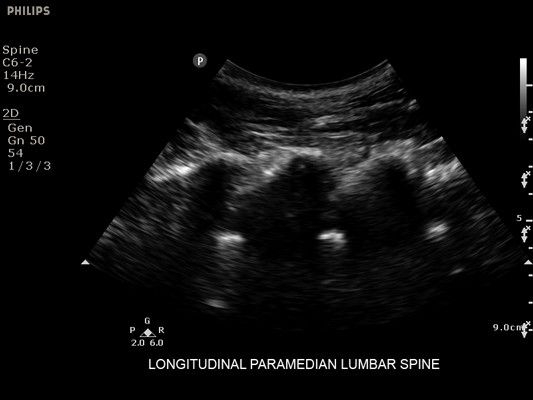

• Технология SonoCT объединяет несколько изображений, полученных под разными углами, создавая единое изображение исключительного качества с минимумом артефактов

• Технология XRES обеспечивает четкость контуров и минимизацию шумов

• Функция AutoSCAN автоматически определяет тип ткани и оптимизирует усиление изображения в процессе сканирования

• Усиленная визуализация иглы без потери качества изображения окружающих тканей

• Метки центральной линии на датчиках L12-4 и C6-2 для упрощения внеплоскостной навигации

• Экранная сетка и маркеры глубины для точной оценки расстояний

• Совмещенный вывод изображений M-режима и живого 2D-изображения для улучшенной интерпретации состояния легких

• Диагностика нервов